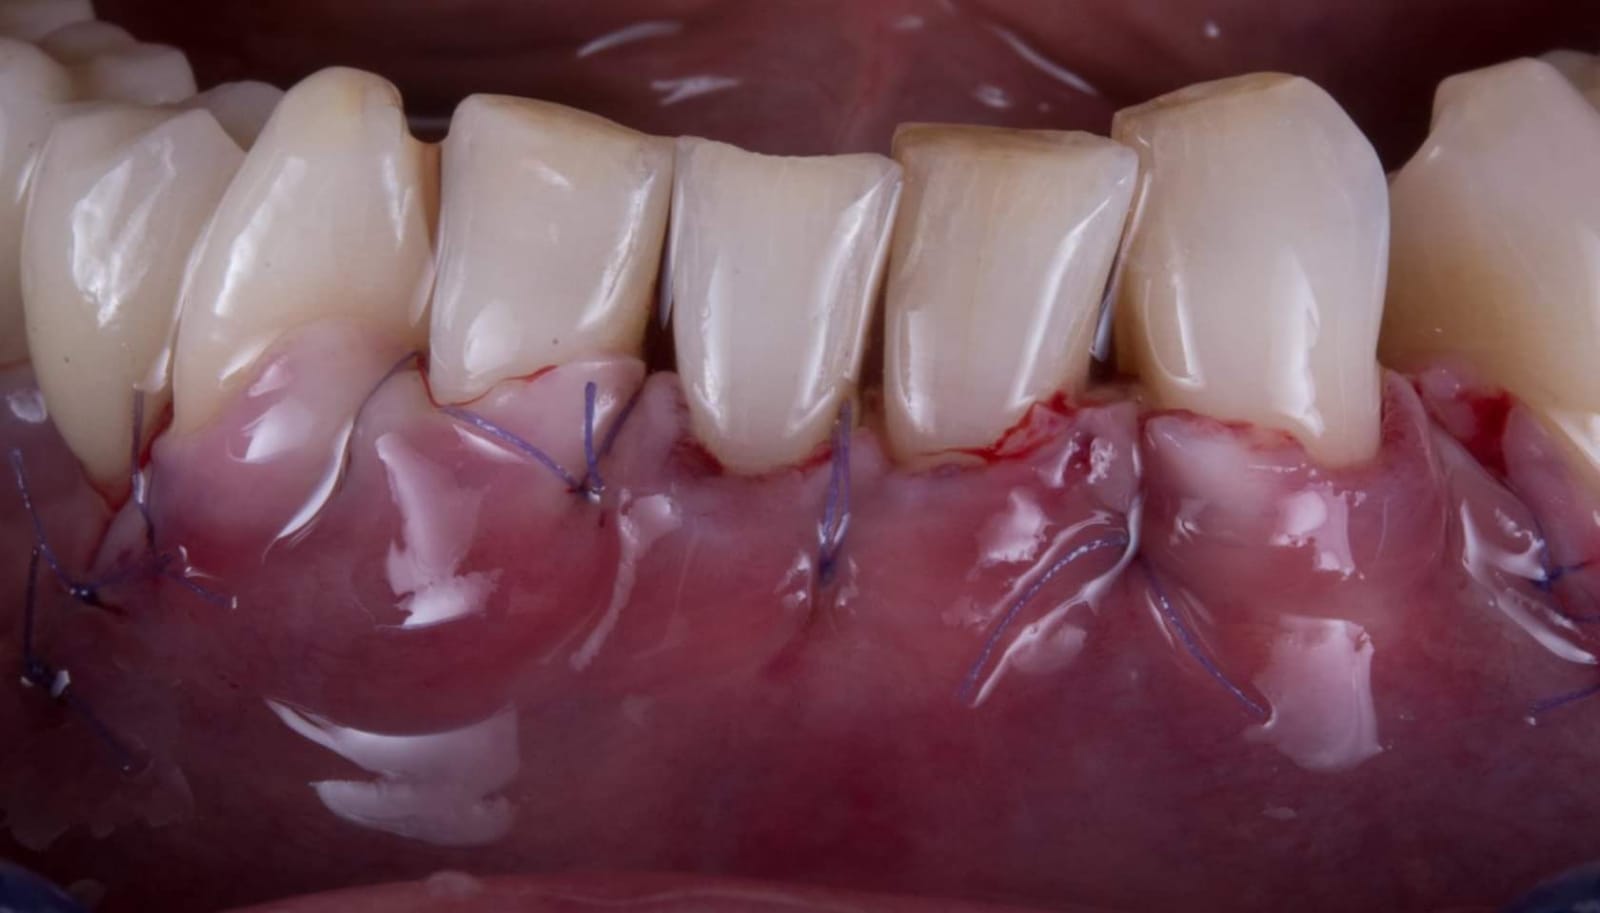

Questa la foto della chirurgia

WhatsApp Image 2019-03-13 at 18.15.31